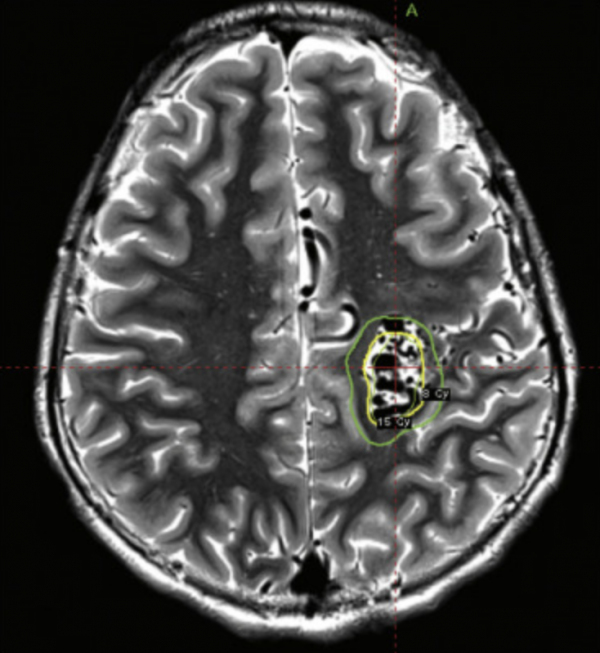

07.09.2025 Zalecenia ESTRO/EANO dotyczące ponownej radioterapii u chorych na glejaka wielopostaciowego.